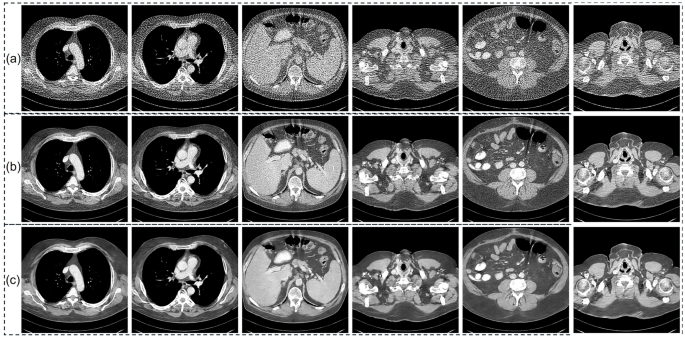

Figure 5a illustrates the 64 projection views reconstructions obtained from the LDCT-and-Projection simulated dataset when all networks are applied without retraining. FBPConvNet suppresses most streak artefacts yet leaves fine anatomical structures unresolved in the enlarged ROIs. FISTA and DUAL reveal more detail, but their outputs exhibit mild blurring, likely due to a domain gap between the training data and the current test case. FreeSeed, which processes data in both the projection and image domains, does not fully correct interpolation errors and therefore retains residual artefacts in soft-tissue regions. MVMS-RCN shows stronger cross-dataset robustness, generating generally clean images, though some structural information is still missing. DRONE benefits from its iterative architecture, achieving noise reduction while keeping many anatomical edges intact. DMAprior, however, presents noticeable artefacts comparable to those seen in FreeSeed, again reflecting insufficient handling of projection-domain interpolation errors. By coupling DMAprior with a physics-guided iterative model, DPMA produces images that align more closely with the reference than any other method in the comparison set.

The quantitative results in Figures 5b and 5c support these visual findings: DPMA reaches the highest PSNR and SSIM values across all evaluated approaches. Consistent with these metrics, the line profiles in Figure 6 show that DPMA’s attenuation curves track the reference intensities most faithfully, confirming its ability to preserve both global contrast and subtle structural variations under this challenging sparse-view, cross-domain scenario.